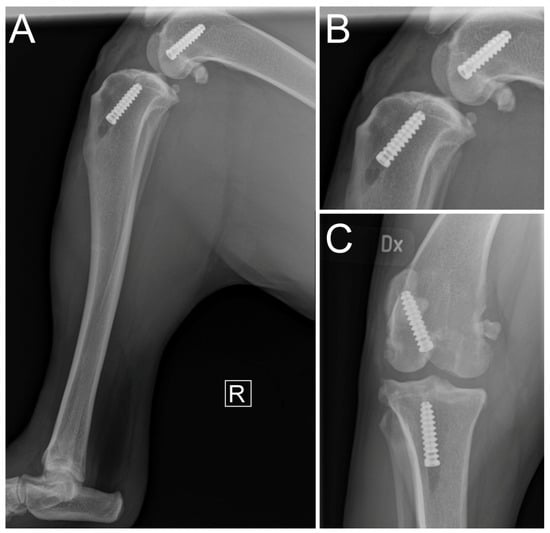

2.5. Immediate Postoperative Evaluation

3. Results